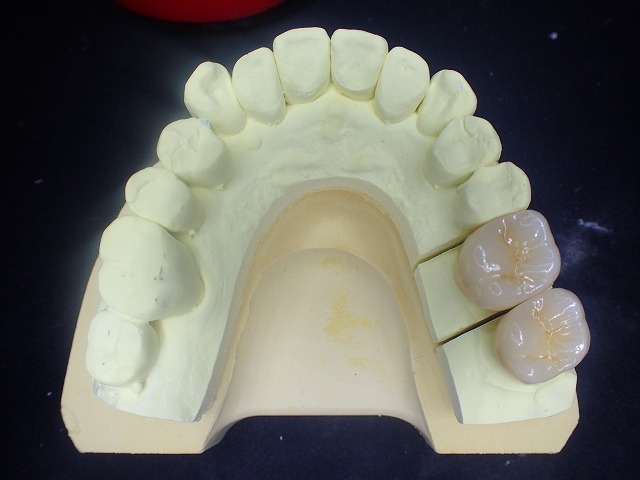

ややピンボケですがしっかりとした土台(コア)

が入っています。

透明度の高いジルコニアボンドクラウン。

透明度が高いので写真がピンボケ

ジルコニアクラン制作

大臼歯のジルコニアクラウン装着